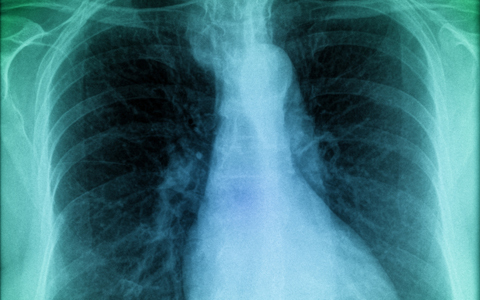

Kísérleti eljárás támaszthatja fel a tüdőt

Évente mintegy 1700 tüdőtranszplantációt végeznek az Egyesült Államokban. Ez a szám jóval magasabb is lehetne, a probléma az, hogy a donorszervek csupán elenyésző számban használhatóak - írja a Fox News.

'Jelenleg a felajánlott donorszervek mintegy 20 százalékát tudjuk használni' - mondta Dr. Kenneth McCurry, a Cleveland Klinika professzora. 'Nyilvánvaló, hogy ez korlátozza, hogy mennyi betegnek tudunk szervet biztosítani, s nagyon sokan vesztik életüket a várakozás alatt' - tette hozzá.

McCurry tüdő- és szívtranszplantációs sebész elmondta, a sérülés, a fertőzés és a víz teszi használhatatlanná a tüdő donorként való felhasználását. Sok orvos szerint meg lehetne menteni ezeket a tüdőket, így transzplantációra alkalmassá válnának, emberek életét megmentve ezzel.

McCurry kísérleti, laboratóriumi eljárásban egy szív-tüdő gépet alkalmazott, amelyen keresztül oxigént pumpált a tüdőbe, s így visszahozta őket az 'életbe'. A kísérletben használt szervek mintegy 50-60 százaléka így már transzplantálható állapotba került.

A tüdő regenerálódása 2-6 óráig tartott, s a szakember reményét fejezte ki, hogy az eljárást hamarosan engedélyezni fogja az amerikai Élelmiszer-és Gyógyszerügyi Hatóság (FDA).